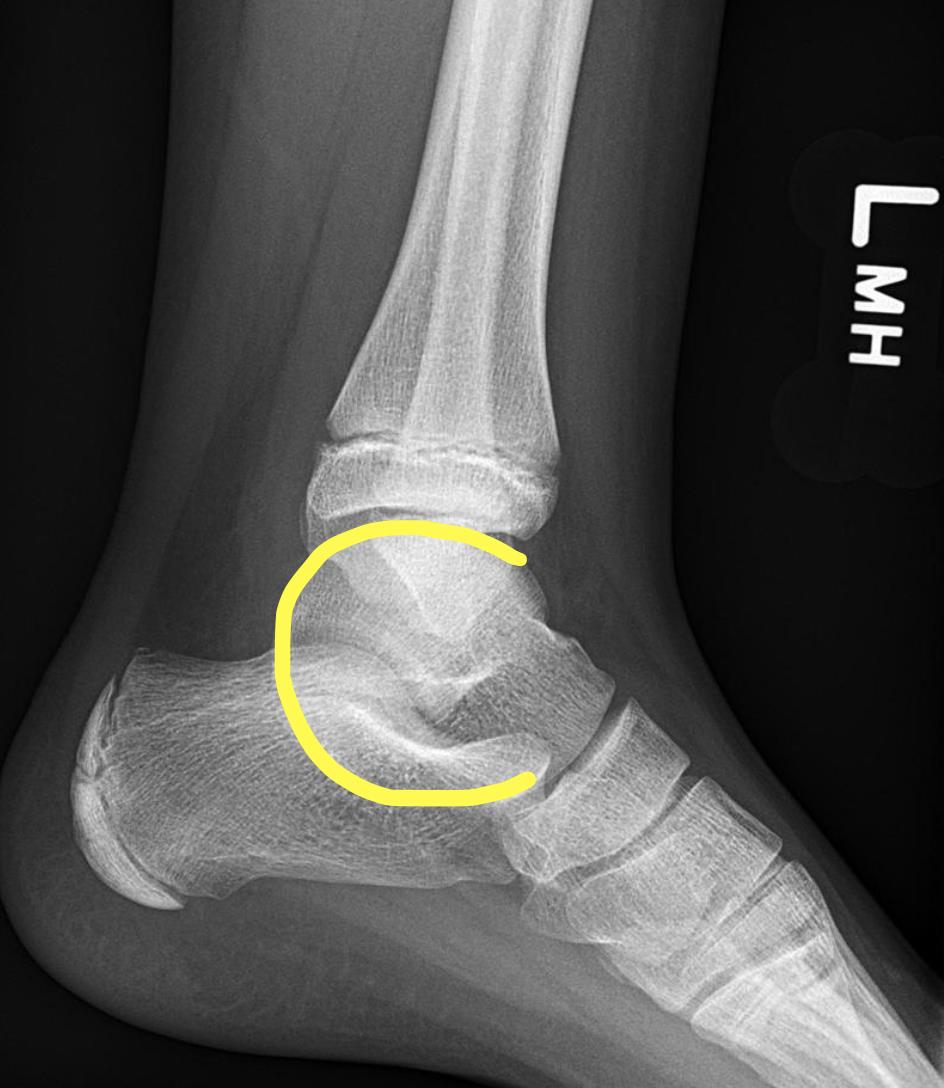

Talocalcaneal coalition is identified by the C-sign (Illustration A) and is caused by failure of mesenchymal segmentation of the subtalar joint.

Tarsal coalitions are most commonly found to be calcaneonavicular (most common) or talocalcaneal. The vast majority, however, are asymptomatic and identified incidentally. When symptomatic, patients commonly report recurrent ankle sprains or persistent activity related pain just distal to the fibula (calcaneonavicular) or distal to the medial malleolus, as is present in this case. Most calcaneonavicular and talocalcaneal coalitions can be identified on plain radiograph as evidence by the anteater sign or C-sign, respectively.

Figure A and B are the AP and lateral radiographs of a pediatric ankle demonstrating the "C-sign" (lateral radiograph), which is indicative of a talocalcaneal coalition. Illustration A outlines this finding.